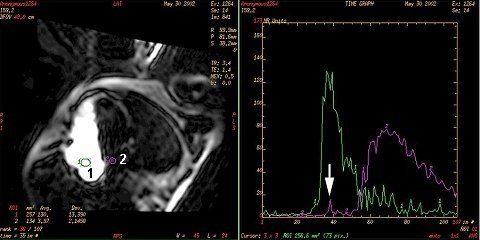

3. Place an ROI in the right atrium (1) and an ROI in the left atrium (2).

4. Press the Spacebar after you deposit each ROI to generate the time/intensity curve.

Figure 1. ROI and time/intensity curve

5. Analyze the curve for a PFO.

• A PFO is typically demonstrated as an additional peak on the time/intensity curve.